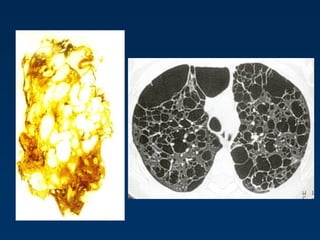

Lymphangioleiomyomatosis (LAM)

HRCT Morphology

Thin-walled cysts (2mm - 5cm)

Uniform in size / rarely confluent

Homogeneous distribution

Chylous pleural effusion

Lymphadenopathy

in young women